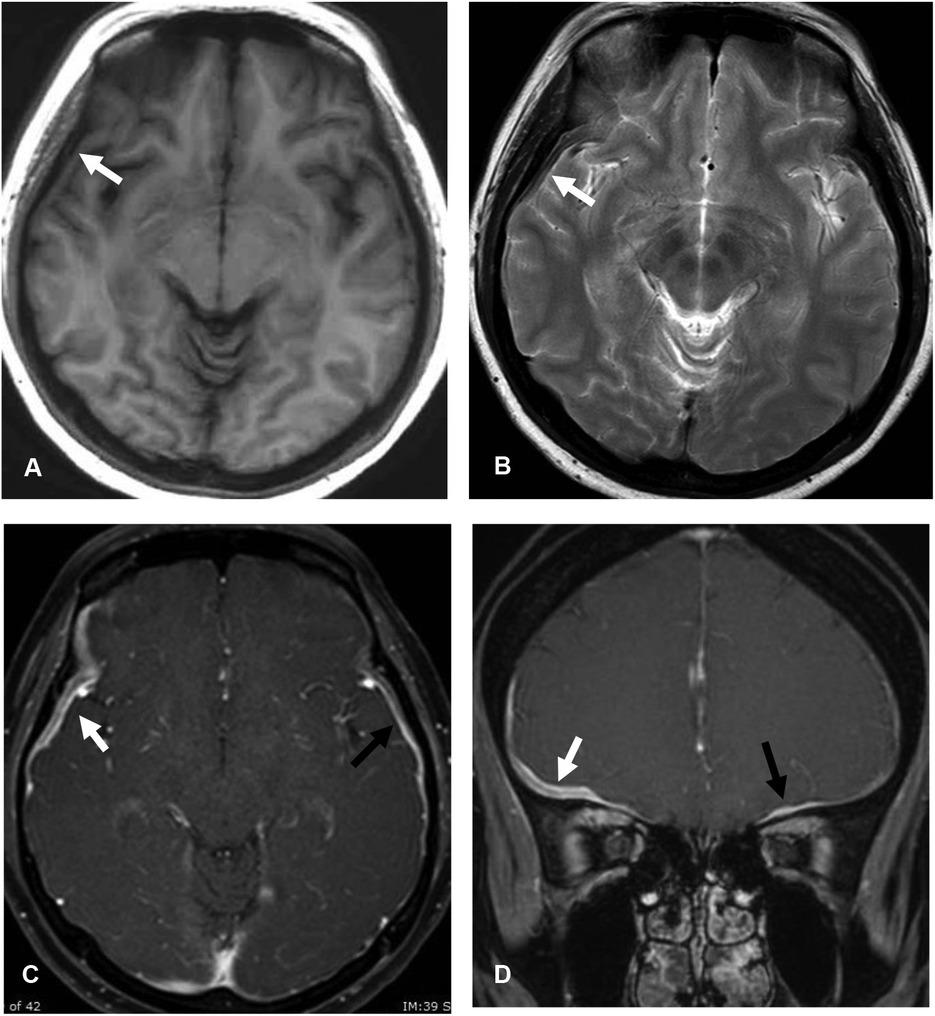

Signal intensity of dural thickening in idiopathic HP and secondary HP groups

| Signal intensity | IHP | Secondary HP | P |

|---|---|---|---|

| (N = 23) | (N = 11) | ||

| n (%) | n (%) | ||

| T1-weighted image | 15 (65) | 9 (82) | 0.784 |

| Iso-intensity | 7 (30) | 2 (18) | |

| Hypo-intensity and dark intensity | 1 (4) | 0 | |

| Hyperintensity | |||

| T2-weighted image | 5 (22) | 3 (27) | 0.148 |

| Iso-intensity | 12 (52) | 3 (27) | |

| Hypo-intensity and dark intensity | 3 (13) | 5 (46) | |

| Hyperintensity | 3 (13) | 0 | |

| T2-rim pattern | |||

| Diffusion-weighted image | 12 | 10 | 0.455 |

| Restricted diffusion | 0 | 1 (10) | |

| No restricted diffusion | 12 (100) | 9 (90) | |

| Enhancement pattern | 16 (70) | 5 (46) | 0.344 |

| Homogeneous | 5 (22) | 5 (46) | |

| Heterogeneous | 2 (9) | 1 (9) | |

| Rim | |||

| T2 hypo-/dark intensity with | 12 | 3 | 0.014* |

| Homogeneous enhancement | 9 (75) | 0 | |

| Heterogeneous enhancement | 2 (17) | 3 (100) | |

| Rim enhancement | 1 (8) | 0 |